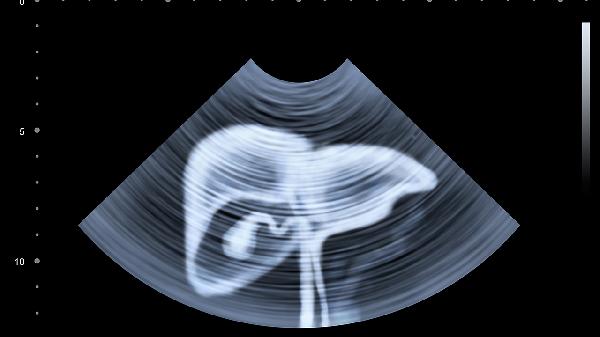

腹部B超一般能检查出肝脏、胆囊、胰腺、脾脏、肾脏等器官的病变情况。检查内容主要有肝胆疾病、胰腺病变、脾脏异常、肾脏疾病、腹水与血管异常等。

腹部B超可检测肝脏肿大、脂肪肝、肝硬化、肝囊肿、肝血管瘤等肝脏病变。对于胆囊,能清晰显示胆囊结石、胆囊息肉、胆囊炎等常见问题。检查时通过回声特征判断病变性质,如结石呈现强回声伴声影,囊肿则为无回声区。

胰腺检查可发现胰腺炎、胰腺囊肿、胰腺肿瘤等异常。急性胰腺炎时可见胰腺弥漫性增大伴回声减低,慢性胰腺炎可能出现胰管扩张或钙化灶。对于胰腺癌,B超能观察肿瘤位置、大小及周围血管侵犯情况。

通过B超可评估脾脏大小、位置及内部结构异常。脾肿大常见于感染、血液病或门脉高压,脾梗死表现为楔形低回声区,脾囊肿或血管瘤则呈现特征性影像改变。对于外伤患者还能判断是否存在脾破裂出血。

肾脏检查能发现肾结石、肾囊肿、肾积水、肾肿瘤等病变。肾结石表现为强回声伴声影,肾癌多呈现低回声团块。对于肾积水可测量肾盂分离程度,慢性肾病晚期可出现肾脏萎缩和皮质变薄。

B超对腹腔游离液体高度敏感,能检测少量腹水并初步判断性质。血管方面可观察腹主动脉瘤、门静脉扩张等异常,彩色多普勒还能评估血管血流动力学改变。对于肠系膜血管栓塞等急症也有重要诊断价值。